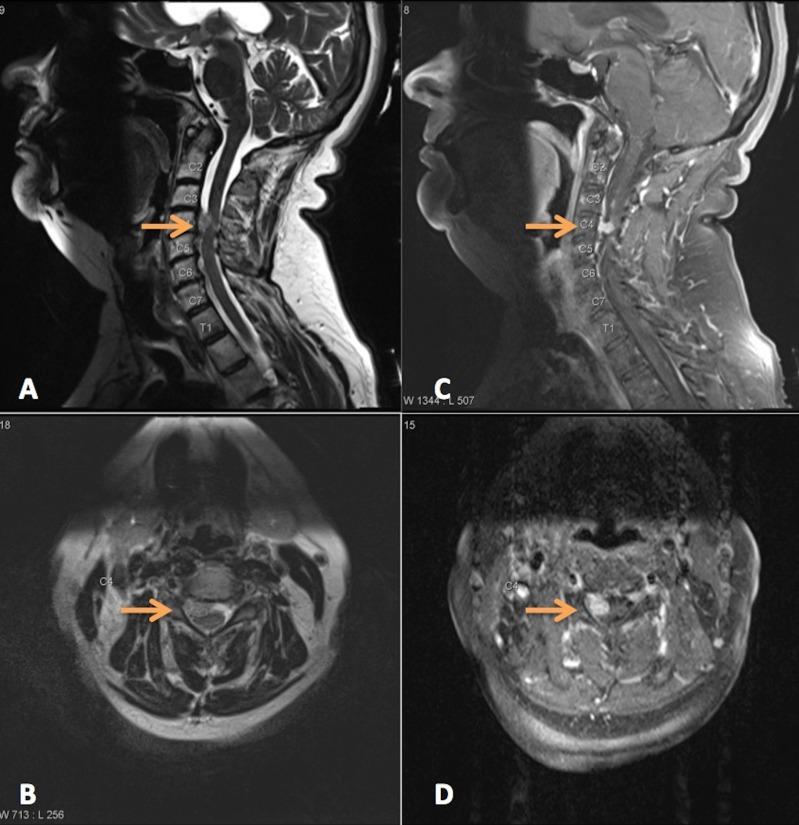

滤泡性甲状腺癌罕见的硬脊膜内颈神经根转移

Rare Intradural Cervical Nerve Root Metastasis of Follicular Thyroid Carcinoma.

Intradural extramedullary nerve root metastasis is extremely unusual with only a handful of cases reported, and it presents most commonly in the thoracic and lumbosacral regions. We report the first case of metastasis to a ventral cervical nerve root in a patient with low-grade follicular thyroid carcinoma thought to be in remission for several years. Histopathology demonstrated malignant transformation and invasion of the nerve root. This case underscores that any history of malignancy regardless of staging, grading, or remission status should raise the suspicion of metastasis as it can mimic other spine and nerve sheath tumors and represent malignant transformation. Gross total resection can be safely achieved with intraoperative neuromonitoring and result in improved function; however, treatment is likely palliative.

摘要

硬脊膜内髓外神经根转移极为罕见,仅有少数病例报道,最常见于胸段和腰骶段。我们报告了首例低级别滤泡性甲状腺癌患者发生颈前神经根转移的病例,该患者被认为已缓解数年。组织病理学显示神经根发生恶性转化并受侵犯。该病例强调,任何恶性肿瘤病史,无论分期、分级或缓解状态如何,都应引发转移的怀疑,因为它可能模仿其他脊柱和神经鞘肿瘤,并代表恶性转化。术中神经监测下可安全实现全切除,并改善功能;然而,治疗可能是姑息性的。